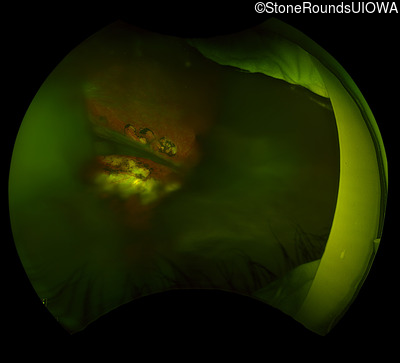

Fundus Photography - Right - 20/300

Exemplar